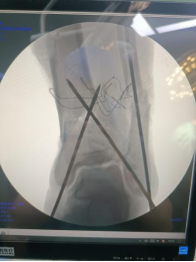

術(shù)中透視脛腓骨遠端,予以克氏針臨時固定。